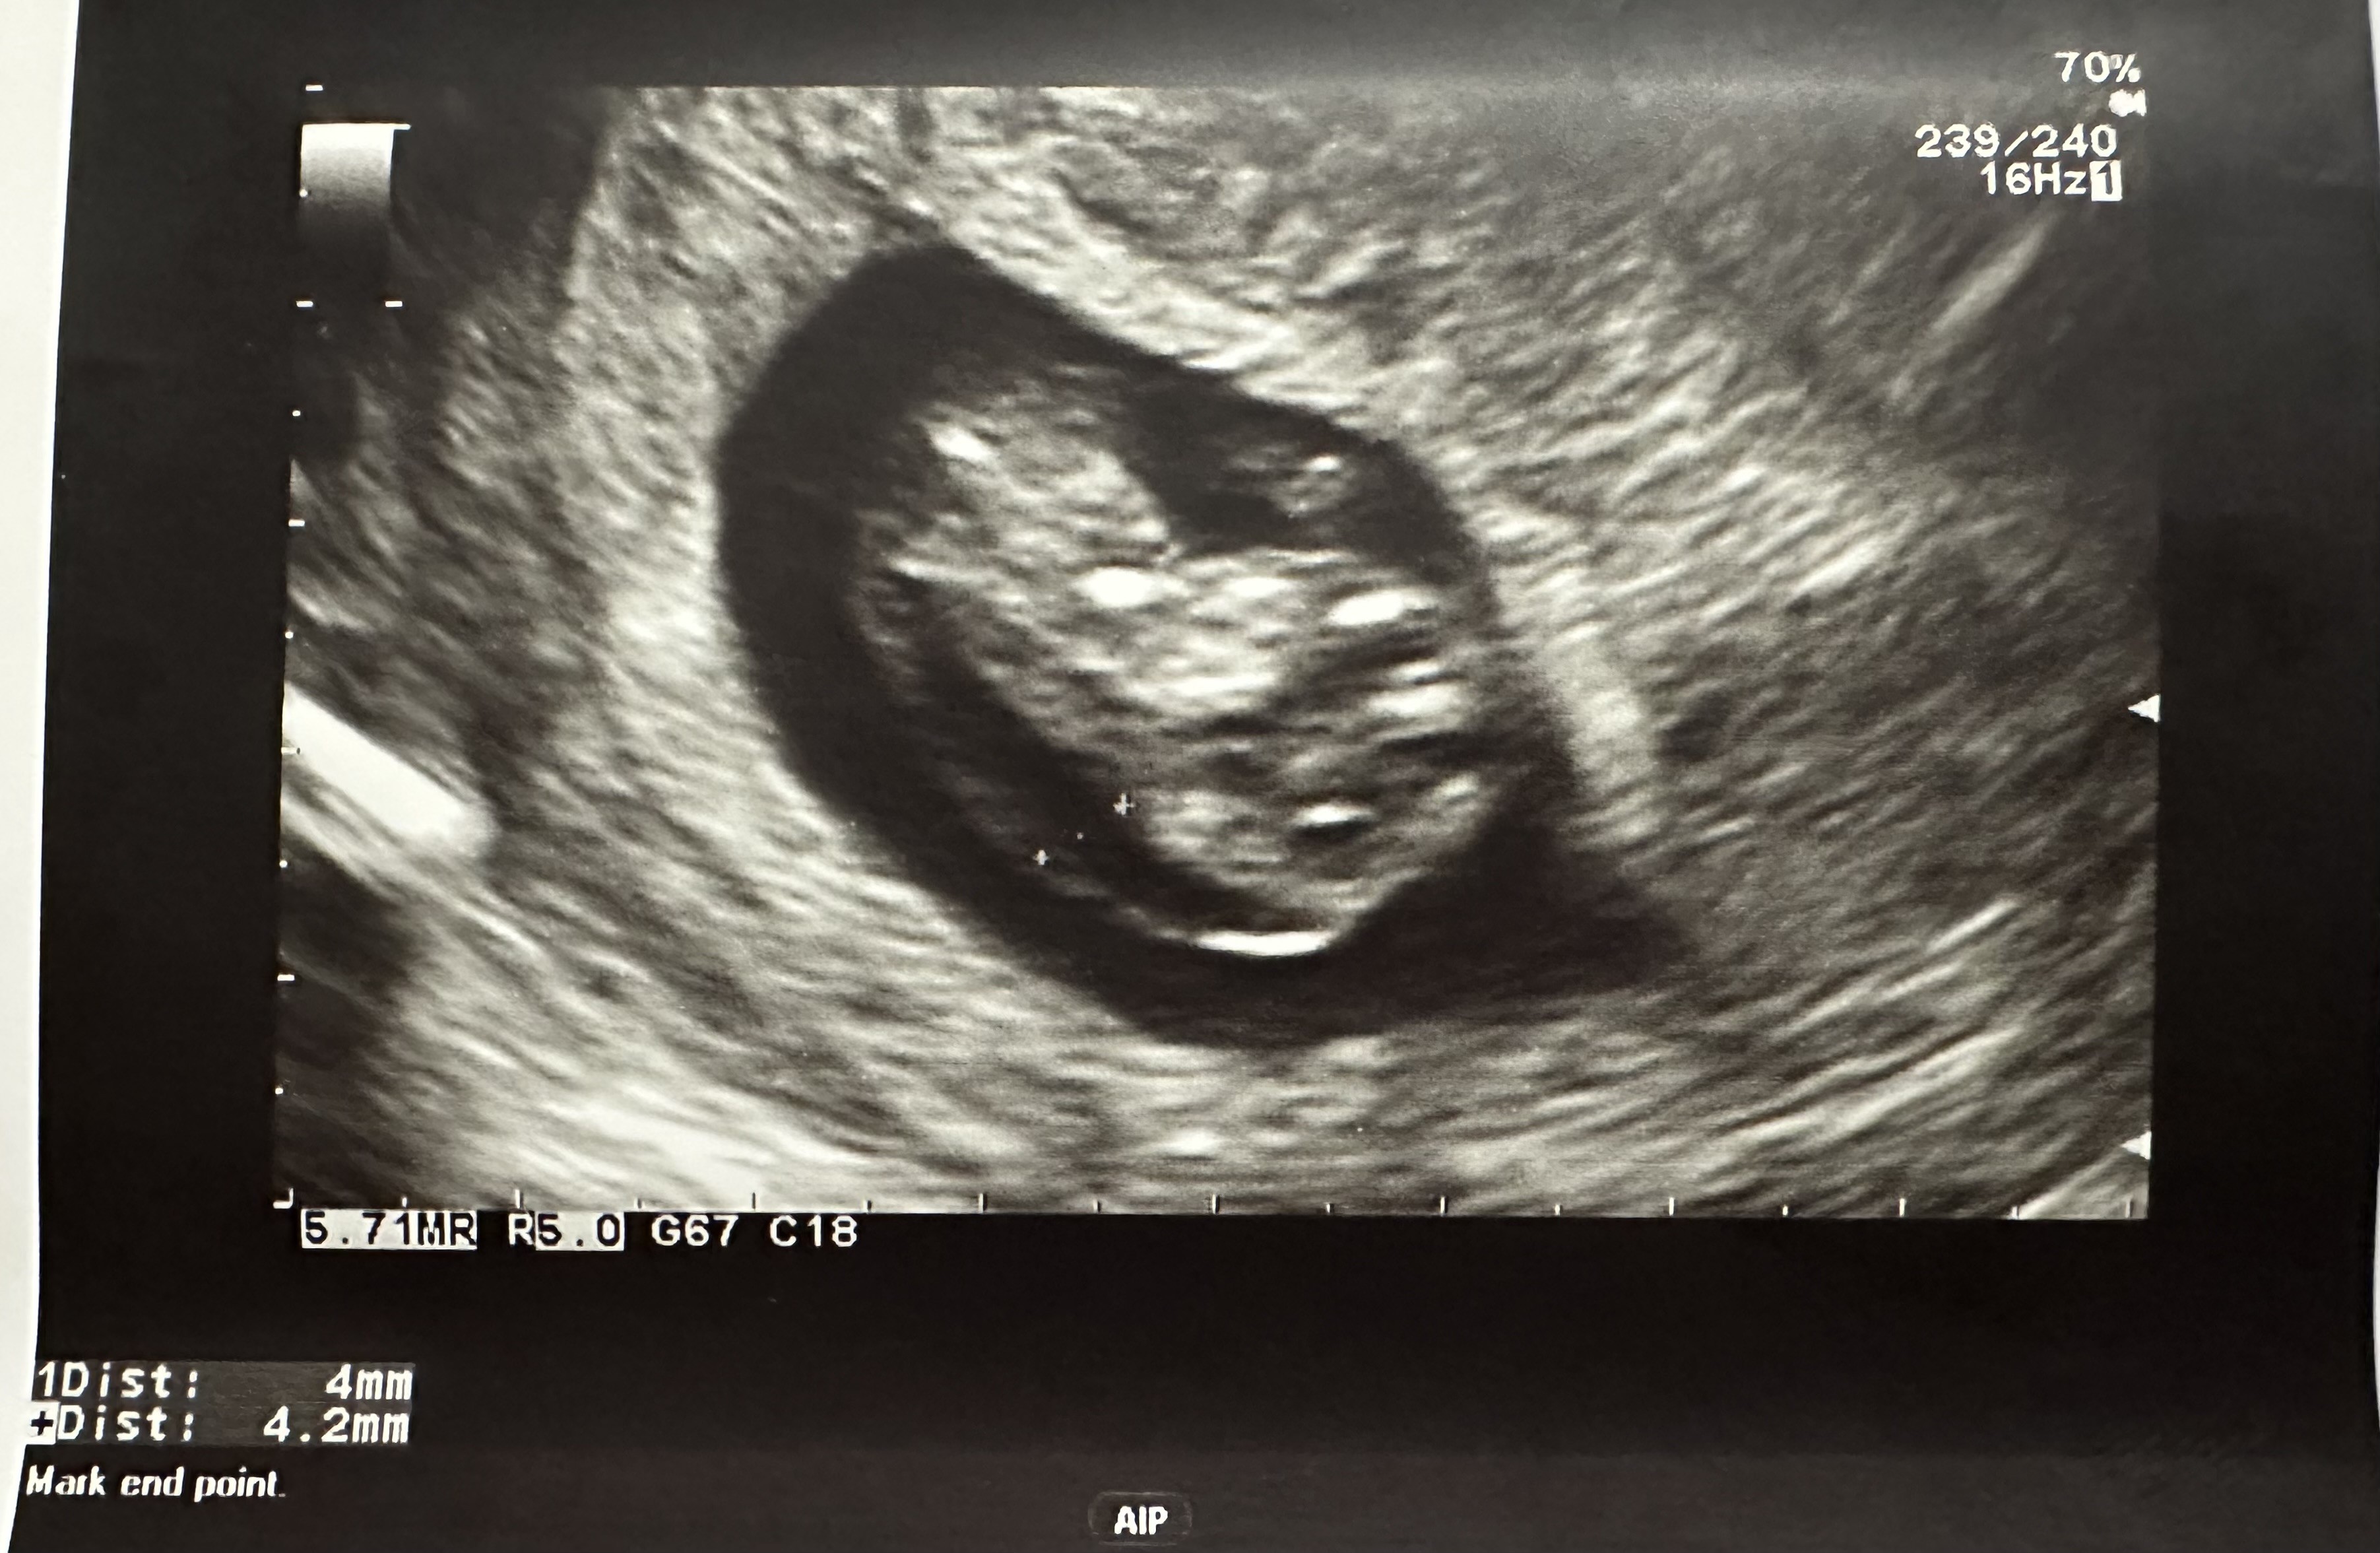

Witam! Mam podobny problem. Byłam na USG w poniedziałek i zdjęcie USG bardzo podobne. Podsyłam w załączniku. W poniedziałek idę na test Nifty, a za tydzień na badania prenatalne na NFZ. Czy możesz powiedzieć co okazało się przyczyna? Mam podobne odczucie - naczytałam się za dużo na temat obrzęku i bardzo się boję. Choć Twoja wiadomość bardzo mnie uskrzydliła! PozdrawiamJa w pierwszej ciąży w 10 tc na badaniu w luxmedzie też usłyszałam, że jest obrzęk - no i lekarka się mnie pytała, czy byłam chora/miałam jakieś infekcje. Akurat byłam zdrowa, więc przez 2 kolejne dni jak się naczytałam o obrzęku płodu to wiadomo, nie było za ciekawieJeszcze wyjeżdżałam na 2 tyg za granicę na urlop i nie miałam jak zrobić USG np za tydzień. Kolejnego dnia byłam na jeszcze jednym USG i ten obrzęk też był widoczny. Na dzień przed wyjazdem zrobiłam Nifty, wyniki przyszły pod koniec urlopu, że jest wszystko ok

poniżej moje USG z tego okresu.

Zobacz załącznik 1603751